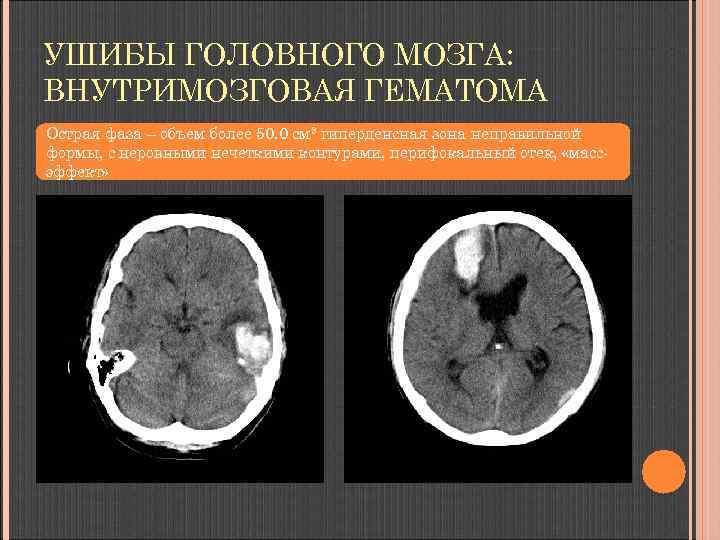

УШИБЫ ГОЛОВНОГО МОЗГА: ВНУТРИМОЗГОВАЯ ГЕМАТОМА Острая фаза – объем более 50. 0 см 3 гиперденсная зона неправильной формы, с неровными нечеткими контурами, перифокальный отек, «массэффект»

УШИБЫ ГОЛОВНОГО МОЗГА: ВНУТРИМОЗГОВАЯ ГЕМАТОМА Острая фаза – объем более 50. 0 см 3 гиперденсная зона неправильной формы, с неровными контурами, перифокально - отек, «масс-эффект»